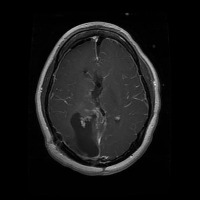

This project has created a labeled MRI brain tumor dataset for the detection of three tumor types: pituitary, meningioma, and glioma. The dataset contains 2443 total images, which have been split into training, validation, and test sets. The training set has 1695 images, the validation set has 502 images, and the test set has 246 images.

- Image types: MRI scans

Classes:

- Pituitary tumor

- Meningioma tumor

- Glioma tumor

- No Tumor

- The images have been labeled by medical experts using a standardized labeling protocol.

- The labels include the type of tumor and the location of the tumor.